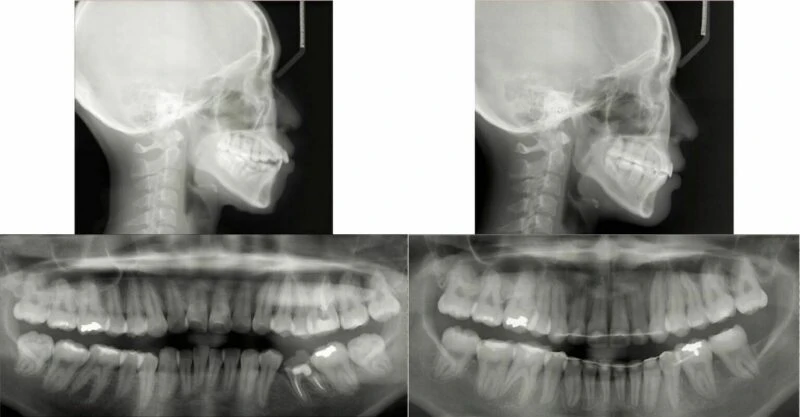

Hình 7 Phim toàn cảnh và phim đo sọ trước điều trị cho thấy môi căng, mất răng 35 và răng 36 điều trị tuỷ không tốt

Hình 8 Phim toàn cảnh và phim đo sọ sau điều trị cho thấy môi cân bằng, độ nghiêng gần-xa chân răng 34 và 47 chưa hợp lý